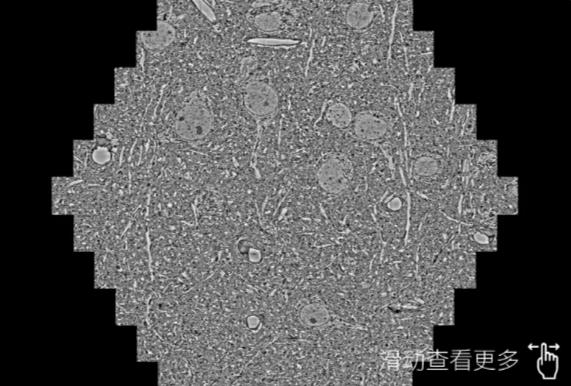

鼠脑切片。左图使用白城蔡司白城扫描电镜MultiSEM706对165μmx143pm面积区域成像,耗时仅需1.5秒。右图为鼠脑切片中30μm区域放大效果。样品由芝加哥大学B.Kasthuri提供。

使用蔡司高速白城扫描电镜MultiSEM对1mm²人脑皮层组织进行高分辨成像,并对其中的各种细胞结构进行三维重构分析。左图展示了2x3mm²组织平面中锥体神经元的三维重构效果。右图显示了局部体积神经元三维重构。图像由哈佛大学chtman实验室提供,渲染图由D. Berger 制作。